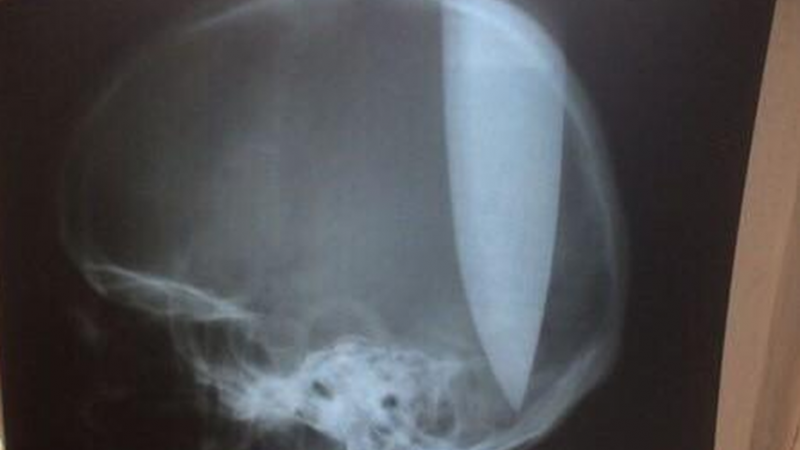

Un hombre que aparentemente tiene trastornos psiquiátricos se clavó un cuchillo de 20 centímetros en la cabeza para “poder respirar”.

Ocurrió en la región rusa de Rostov. Según informó el portal Privet Rostov, fue encontrado por automovilistas locales en un campo de la zona. Tenía el cuchillo clavado en la cabeza y estaba totalmente lúcido.

Según le dijo a la Policía, se clavó el objeto para “poder respirar” tras sufrir una congestión nasal a causa de un largo resfriado.

Los médicos pudieron extraerle el cuchillo e informaron que está estable y fuera de peligro. Estará una semana internado en terapia intensiva y después será derivado a una institución psiquiátrica, según RIA Novosti.